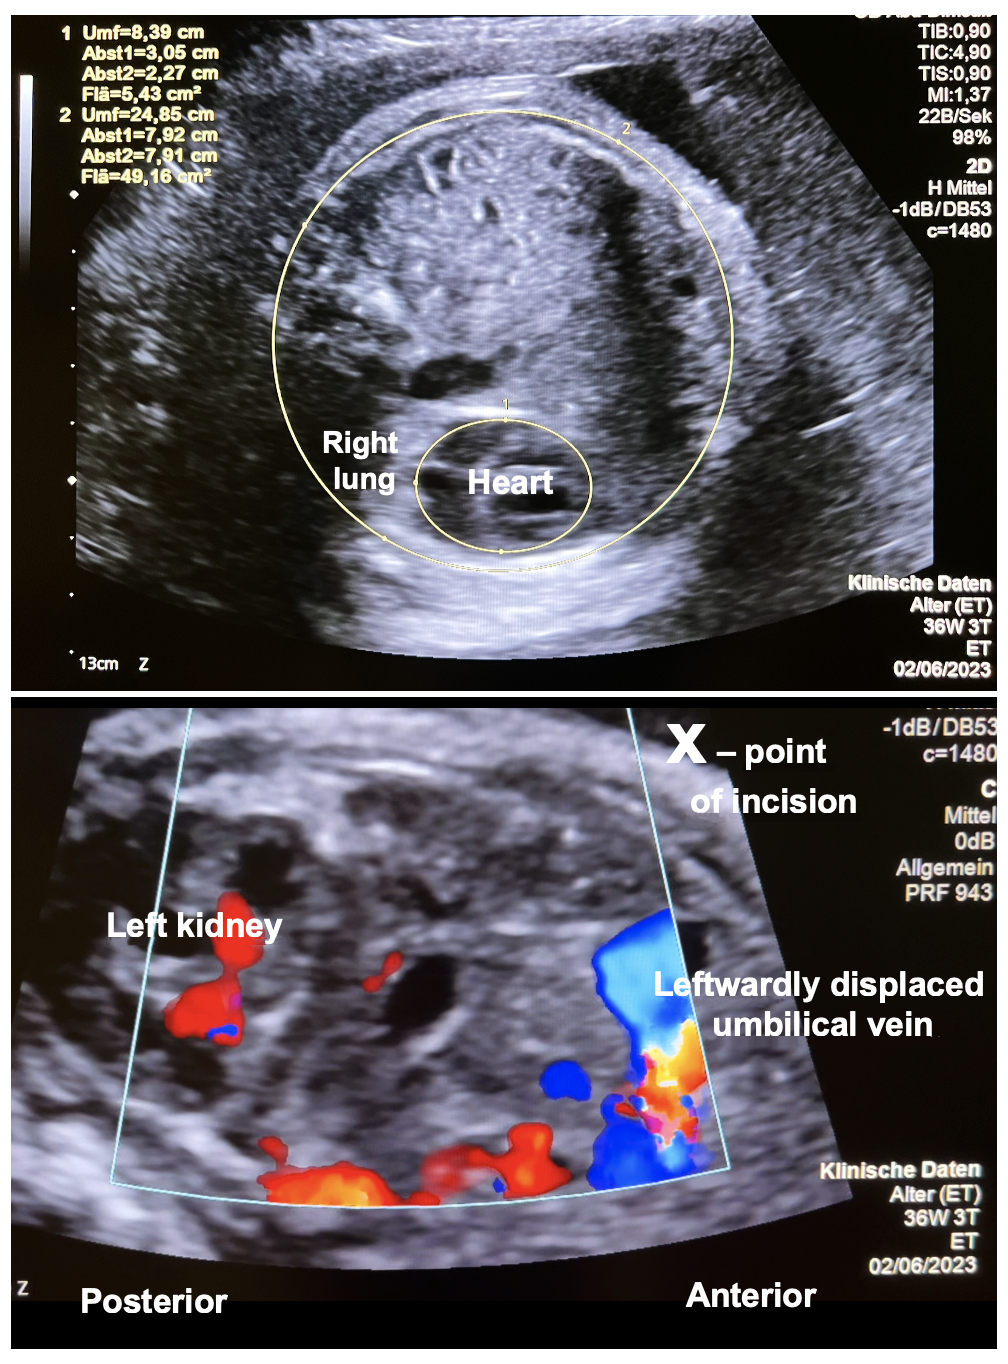

A 27-year-old pregnant woman (gravida 1, para 0) was admitted to our center at 36 + 3 weeks of gestation. In her singleton fetus, a severe left diaphragmatic hernia with an o/e LHR of ≤25% and an MRI lung volume of ≤20%, as well as poor pulmonary perfusion and marked left heart hypoplasia from preferential streaming of ductus venosus/inferior caval vein flow toward the right side of the heart, was observed (Figure 1—top).

Figure 1.

Cross-section through the chest in a human fetus with severe left-sided diaphragmatic hernia at 36 + 3 weeks + days of gestation. (Top)—Note the small area left for the fetal heart and right lung as a result of the large volume of herniated abdominal organs. (Bottom)—Oblique horizontal view of the upper fetal abdomen. This view was taken in order to follow the course of the intraabdominal umbilical vein. Note the close proximity of the left kidney, the leftwardly displaced coursing umbilical vein and the incision site (x). The left lateral vertical incision avoids the risk of injury to the larger abdominal wall vessels.

Employing scissors, monopolar cautery and various graspers, a vertical laparotomy was performed in the anterior axillary line, thus transsecting the oblique and transverse abdominal muscles (Figure 3). Particular care was taken to stay intraperitoneally and anterior to the left kidney. However, as a result of the leftward shift of the liver hilus from the intrathoracic herniation of its left lobe, the greatest care had to be taken not to injure the intraabdominal portion of the umbilical vein that coursed in immediate proximity below the incision site (Figure 1).